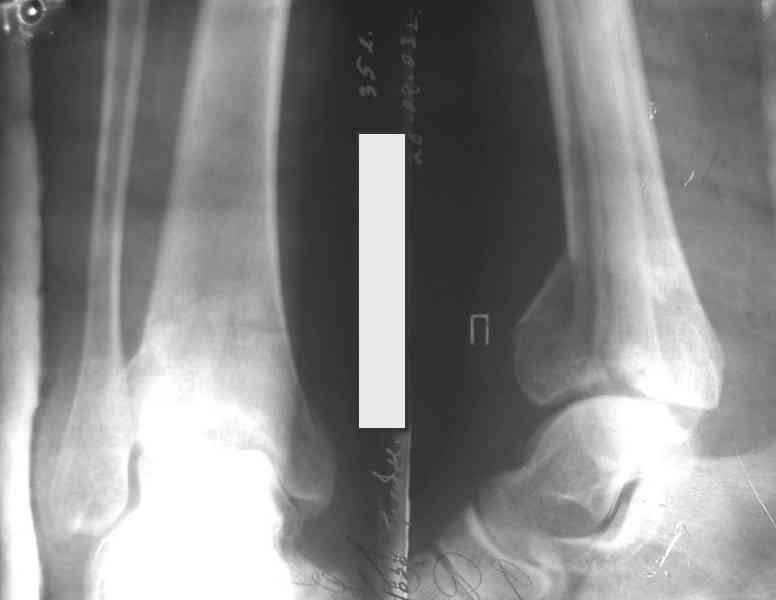

На рентгенограммах типичный перелом пилона по типу С-3. есть опыт до 100 открытых опреаций у нас в клинике. 20 примерно в год. Принцип один -все внутрисуставные переломы нуждаются в открытой репозиции и внутренней стабильной фиксации. При поступлении КТ не надо, так как получается только нагромождение костей. Истинной картины нет. Главное восстановить длину малоберцовой кости - это ключ к успеху. При поступлении меньше всего надо думать о сосудистых расстройствах, т.к. сама операция и репозиция даже сначала частичная даёт улучшение сосудитых нарушений. Причём очень быстро. Операция в 2этапа. При поступлении доступ позади наружной лодыжки, причём обязательно. После этого репозиция малоберцовой кости и фиксация пластиной 1/3 трубки под винт 3,5. Дренаж и любой аппарат наружной фиксации. Затем после спадения отёка на 5-7-10 день аппрат снимается и дугообразный разрез спереди от медиальной лодыжки 10-12 см. Главной чтобы расстояние между 1 и вторым разрезом было не меньше 7-8 см. Тогда не будет некрозов лоскутов. Таранная кость используется как матрица на неё укладываются отломки и фиксируются пицами. Ренг-контроль. Отломки лежат все отдельно, но ничего не высыпется. При переломах С-3 всегда нужна костная пластика (из крыла). Фиксация пластиной лист клевера простой или LCP. Гипс не нужен. Дренаж до 48 часов. Операция длится 3-4 часа обязательно без жгута. Посылаю примерно такой же случай.

Ещё есть одна проблема когда есть перелом малоберцовой кость, то всё ясно. А когда малоберцовая кость не повреждена, то сразу накладывается аппрат наружной фиксации при поступлении, чтобы как бы перерастянуть отломки и главное убрать вальгусное или варусное смещение, а потом на 5-7 день открыто большеберцовая кость восстанавливается и фиксируется пластиной. С уважением Дрягин

Ja operiroval bolnogo po Vashemu, hotia sam ni ochen' ubezden' v itom, t.k. bolnoi otkazalsa na proch' ot ex.fix, ja emu sdelal ORIF + Kostnia plastika, snimky prelogiottsa,